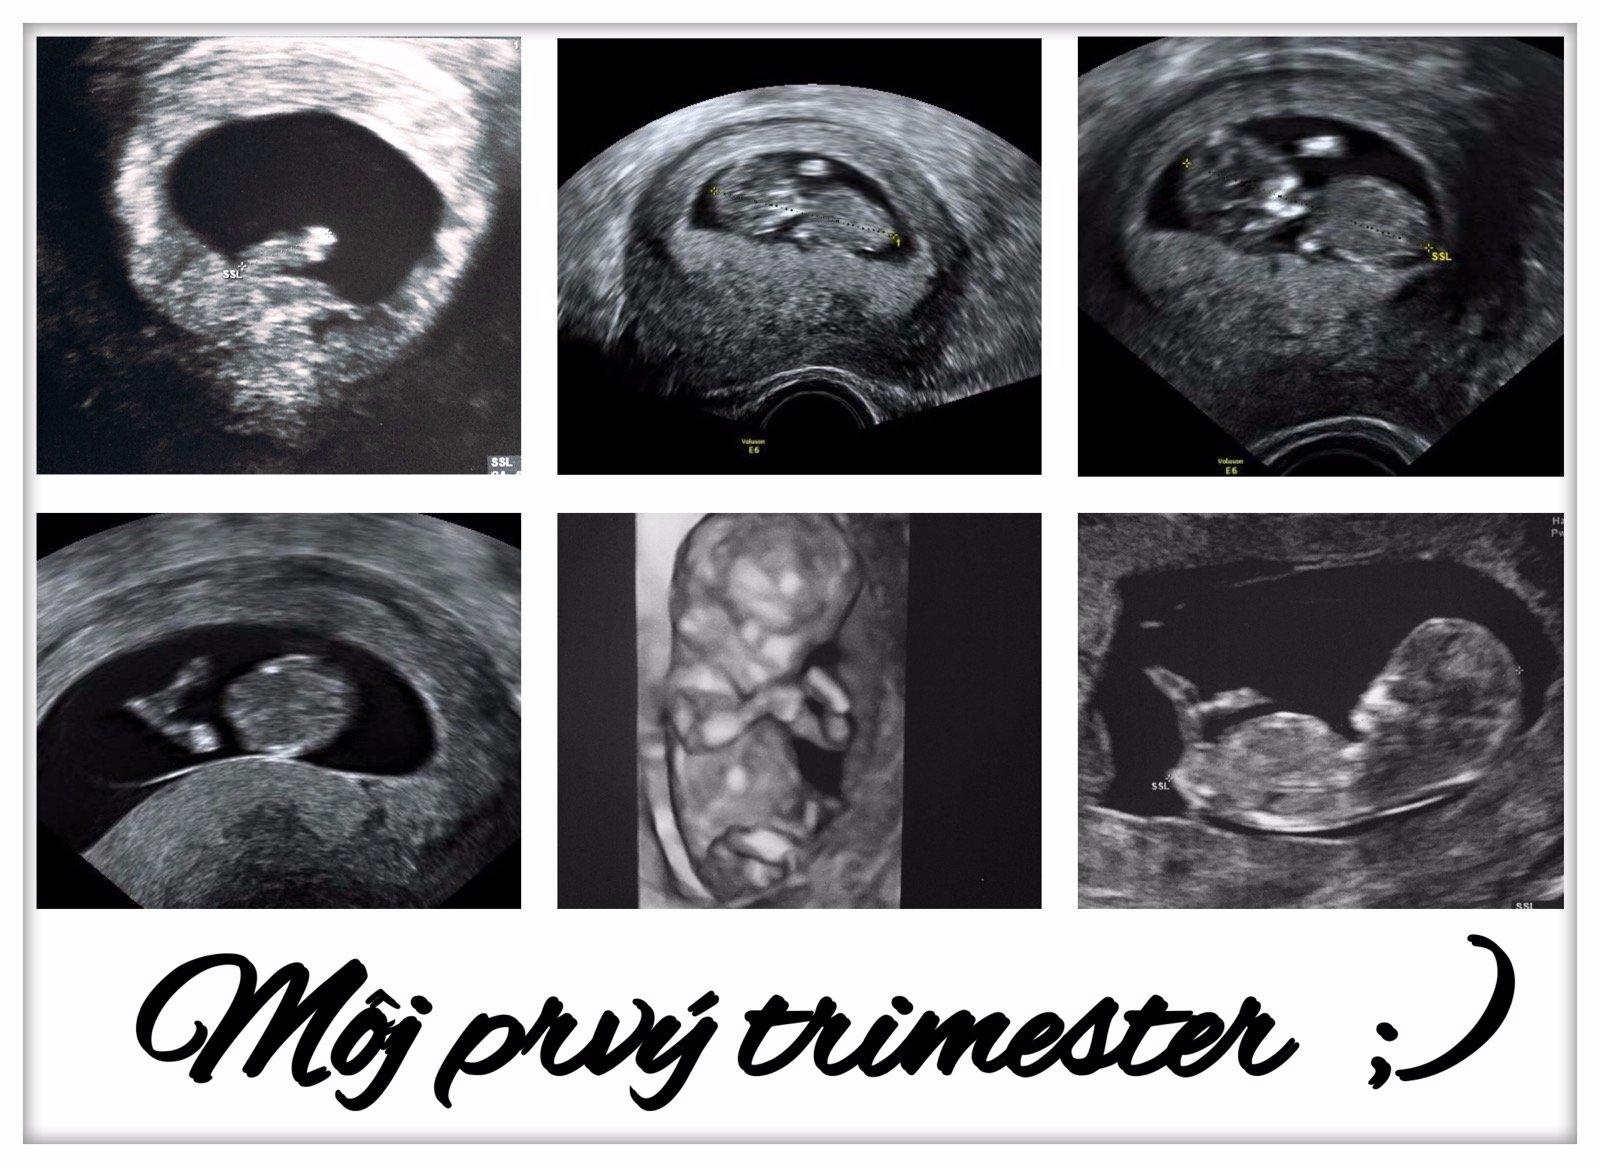

To bude chlapček? 🙂

@sevinka este nevieme 😉 vidíš to podľa niečoho ? 😊

@acernas Na poslednej fotke mi to príde ako močovod dlhý tam ako su nejaké tie mini pidi písmenka, my sme mali na uzv iný tvar a mame dievčatko 🙂

@sevinka ano ten výbežok vraj ak smeruje na hor mal by to byt chlapček ak je to vodorovne alebo smerom na dol dievčatko 😉

@acernas Taký tvar varlatok:D

@sevinka no uvidíme 😉